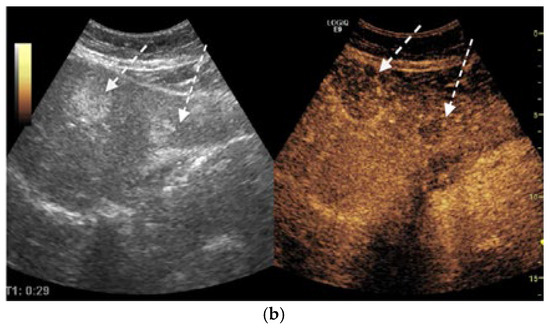

The thoracic contrast-enhanced CT scan provided a para-aortic mediastinal tumor mass with extension into the aortopulmonary window, raising further questions about the nature and origin of the hepatic and cecal lesions. The mediastinal mass was solid, heterogeneous, irregular, lobulated, and exobronchial, measuring 50× 30 × 45 mm. Additionally, lymphadenopathies were identified in the right inferior paratracheal, subcarinal, and paraesophageal regions, as well as adjacent to the left inferior pulmonary vein and the left interlobar area (Figure 5).

Figure 5.

Contrast-enhanced thoracic CT (axial, arterial phase; mediastinal window) demonstrates a lobulated mediastinal mass with heterogeneous enhancement, abutting the right pulmonary artery, measuring approximately 49 × 29 mm in the aortopulmonary window.